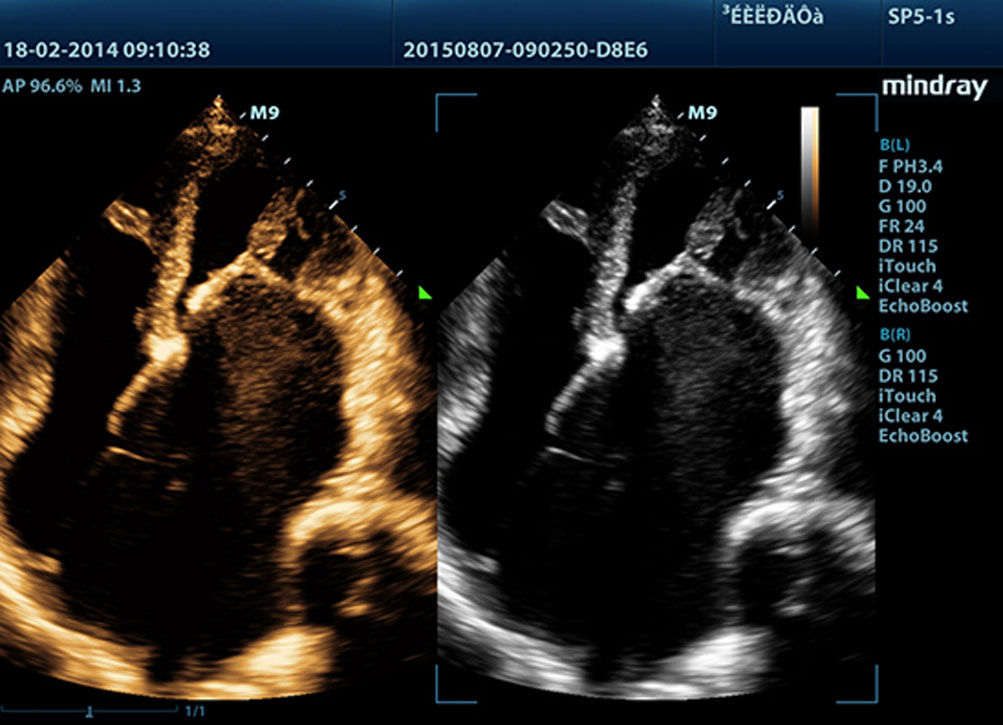

Echo Boost?

MindrayŌĆÖs unique adaptive signal processing technology with intelligent echo detection, designed to utilize the native signal-to-noise information to enhance the weak echo signals while suppressing the surrounding clutter noise, providing more balanced image brightness and improved visualization of myocardium tissue layers.